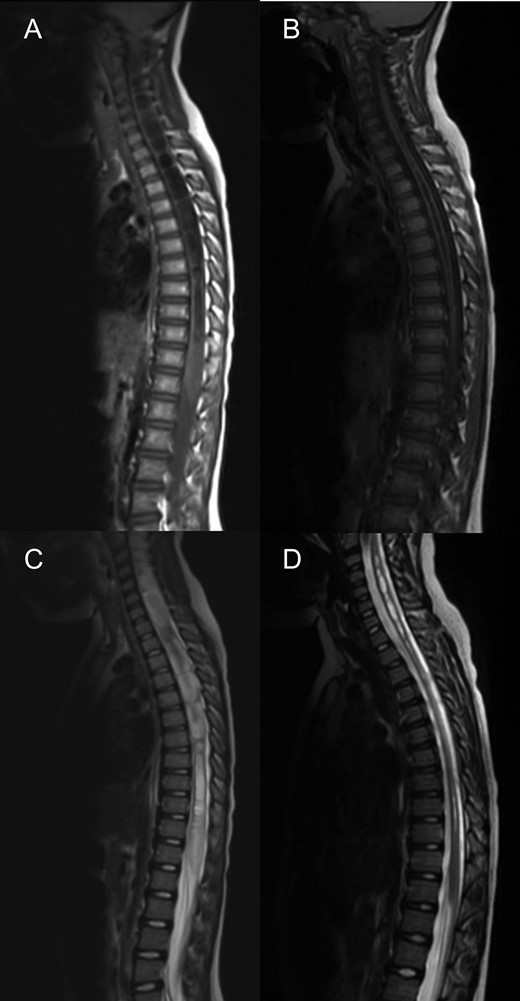

MRI spine sagittal sections demonstrating a holocord syrinx decreasing in size following surgery. Pre (A) and 3 years post op (B) T2. Pre (C) and 3 years post op (D) and T1.

At 1 year follow-up, his foot drop had gradually improved. He was able to walk on his tip toes and heels. By 2 years follow-up, his foot drop had completely resolved and ankle dorsiflexion was 5/5 on the right. An MRI at three years post op demonstrated a good foramen magnum decompression (Fig. 1) and significant improvements in the syrinx (Fig. 2), however not complete resolution.

We observed a reduction in the syrinx volume, which was similar to the other cases described [3–6] however complete radiological resolution of the holocord syrinx has also been described [6].